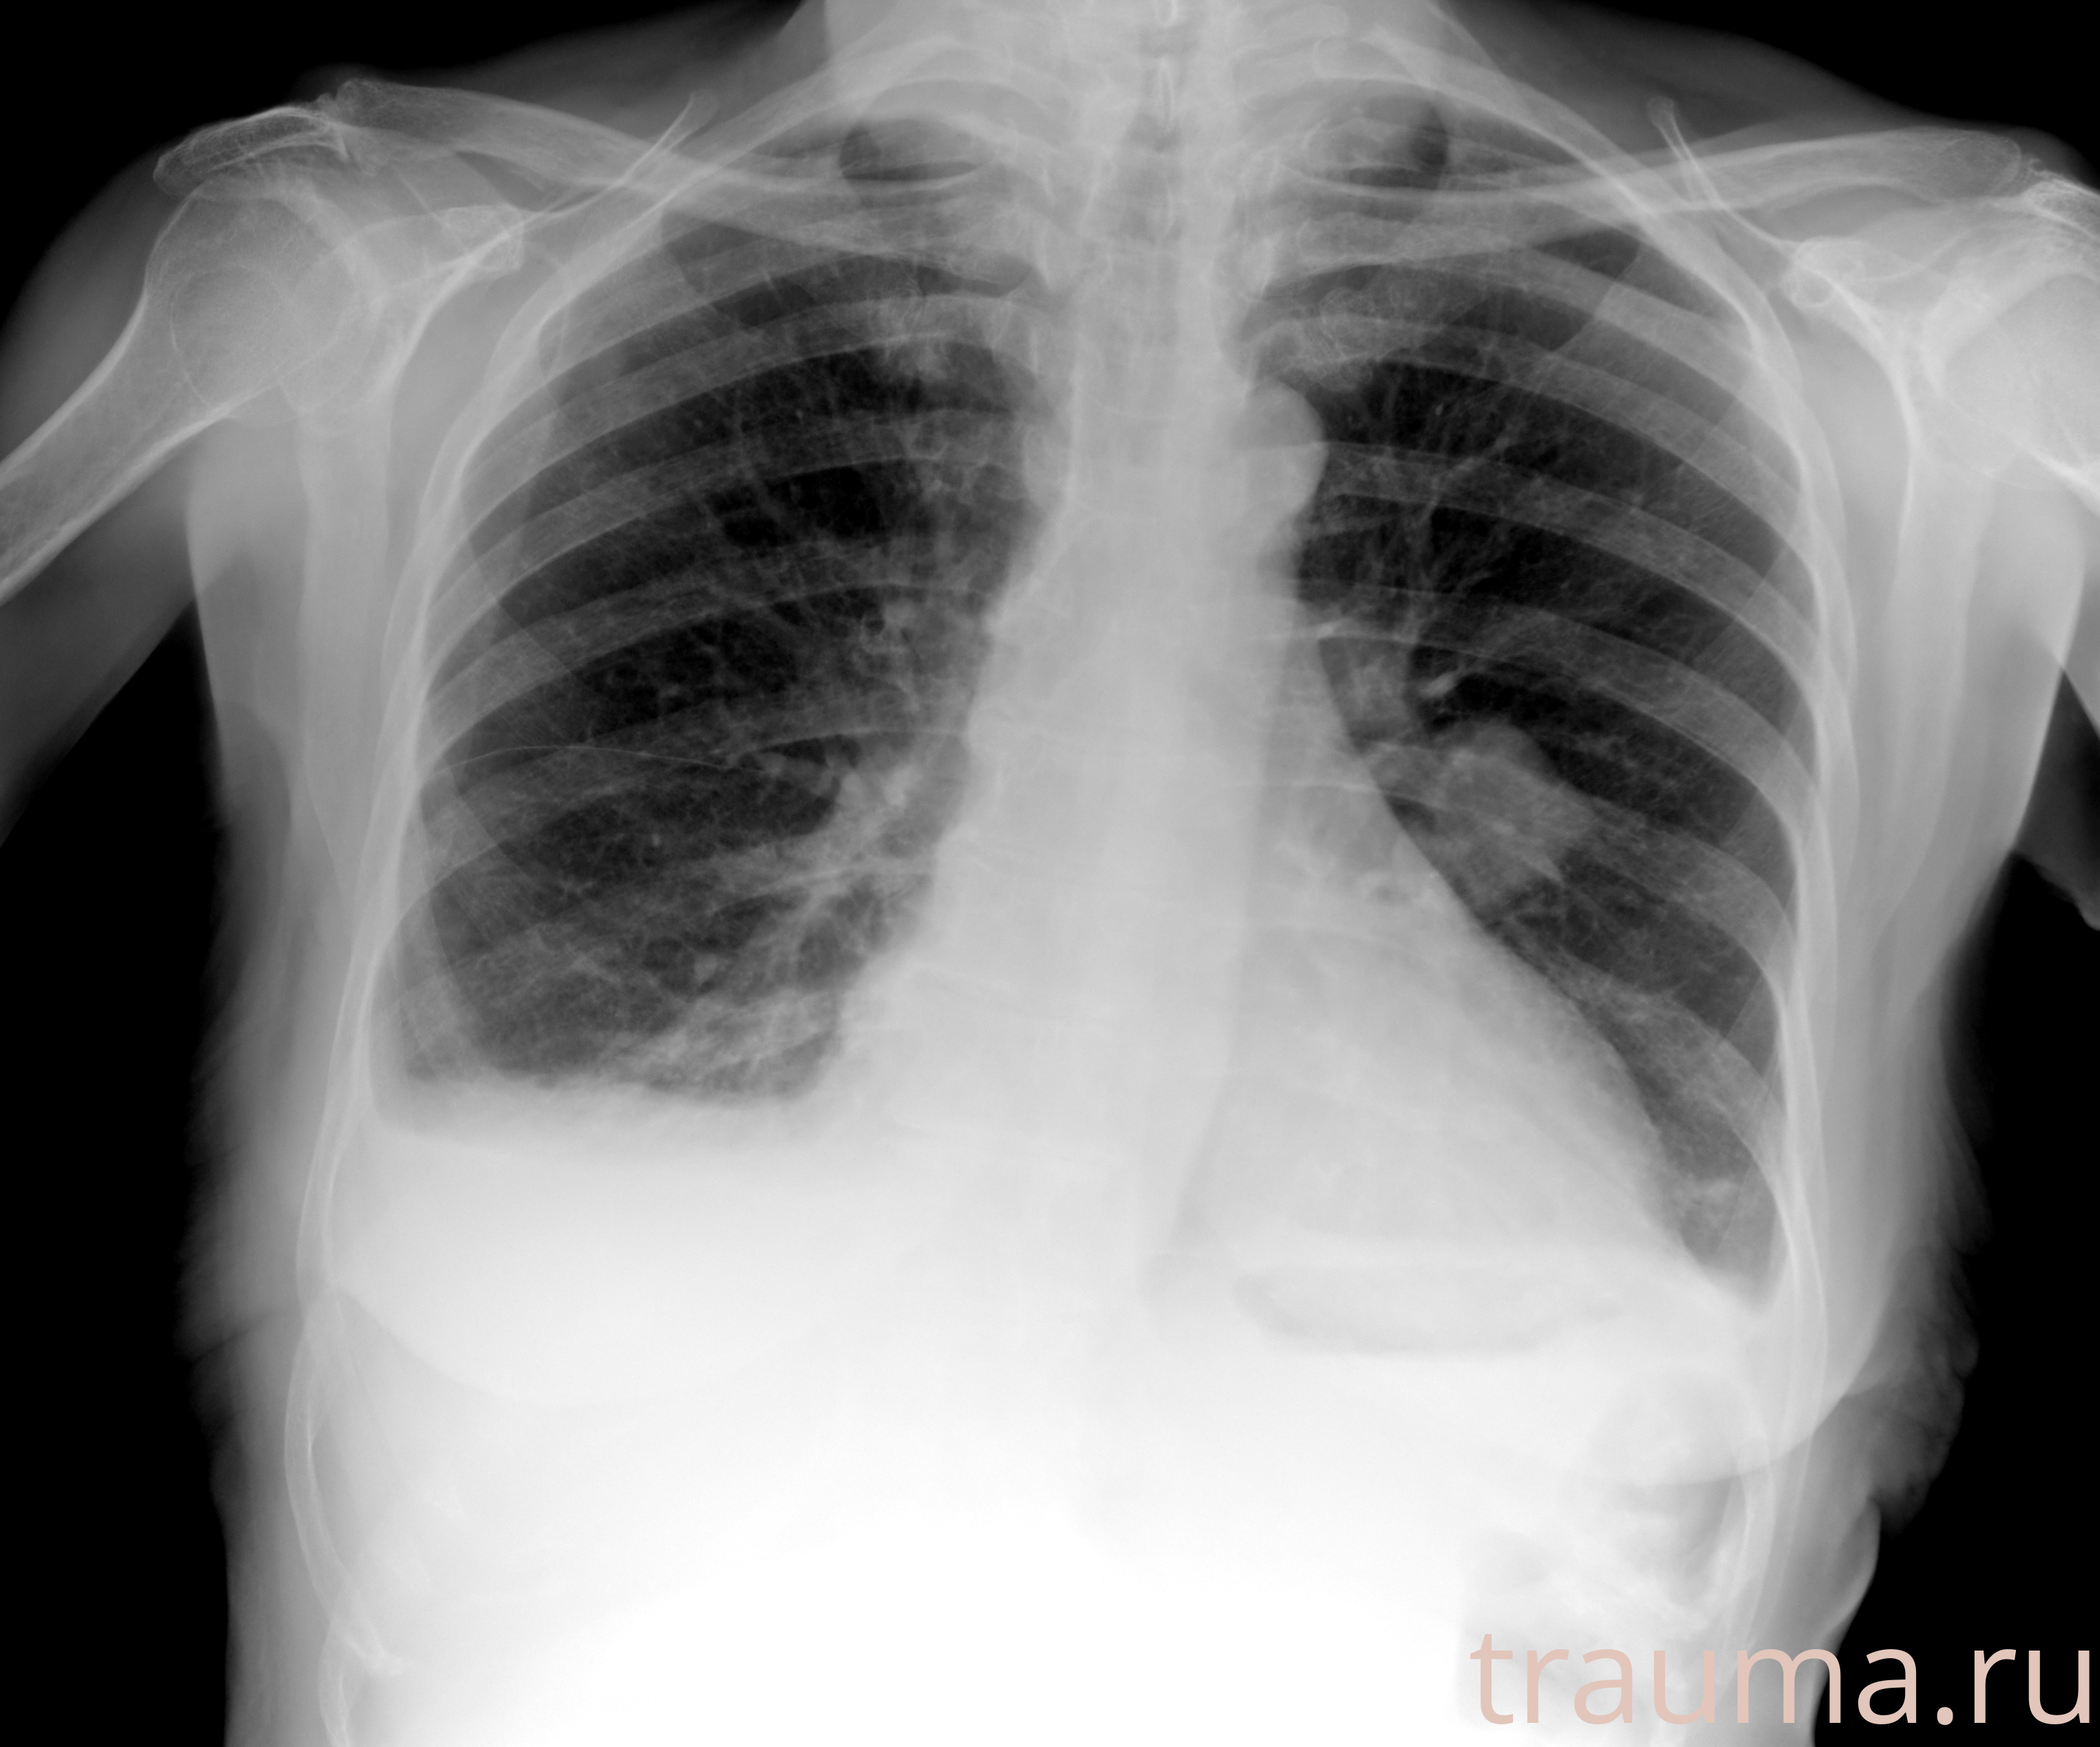

Рентгенограммы

Натуживание 26.12.2025 21:16:34

Рентген на дому: по вашему адресу приезжает врач-рентгенолог, травматолог-ортопед с мобильным рентгеновским аппаратом, проводит диагностику травмы или заболевания, делает необходимые рентгенограммы, дает рекомендации по дальнейшему лечению. Получить качественные снимки в домашних условиях возможно благодаря уникальной методике, разработанной МосРентген Центром для института  Склифосовского